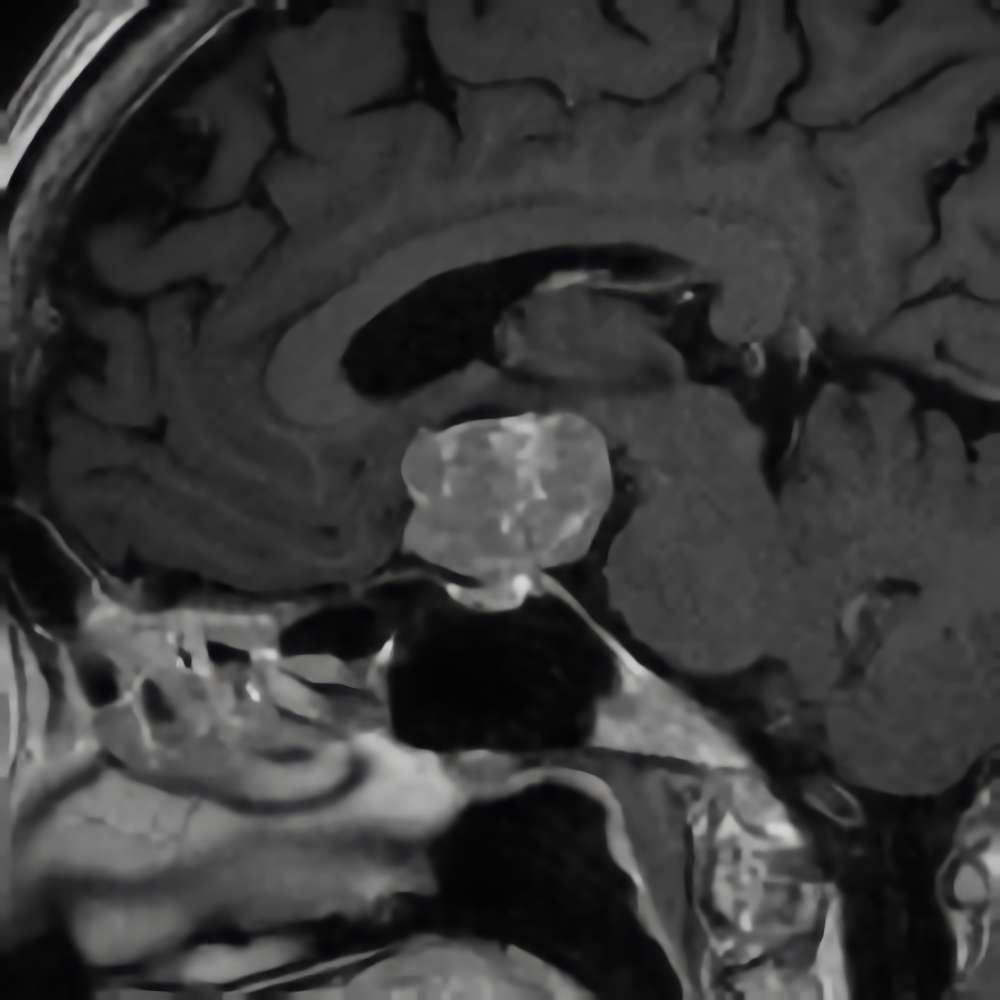

断層撮影

下垂体腺腫

No.’16_38 手術前1